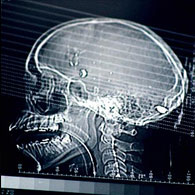

Raio-x mostra bala alojada na cabeça de Eloá

O hospital informa que as duas passaram por cirurgias para extrair os projéteis. A equipe de médicos que operou Eloá opta por manter a bala alojada no crânio porque o procedimento de retirada causaria mais danos. "é um caso muito grave", diz a neurocirurgiã Grace Mary Lydia. Já o estado de saúde de Nayara é considerado bom.